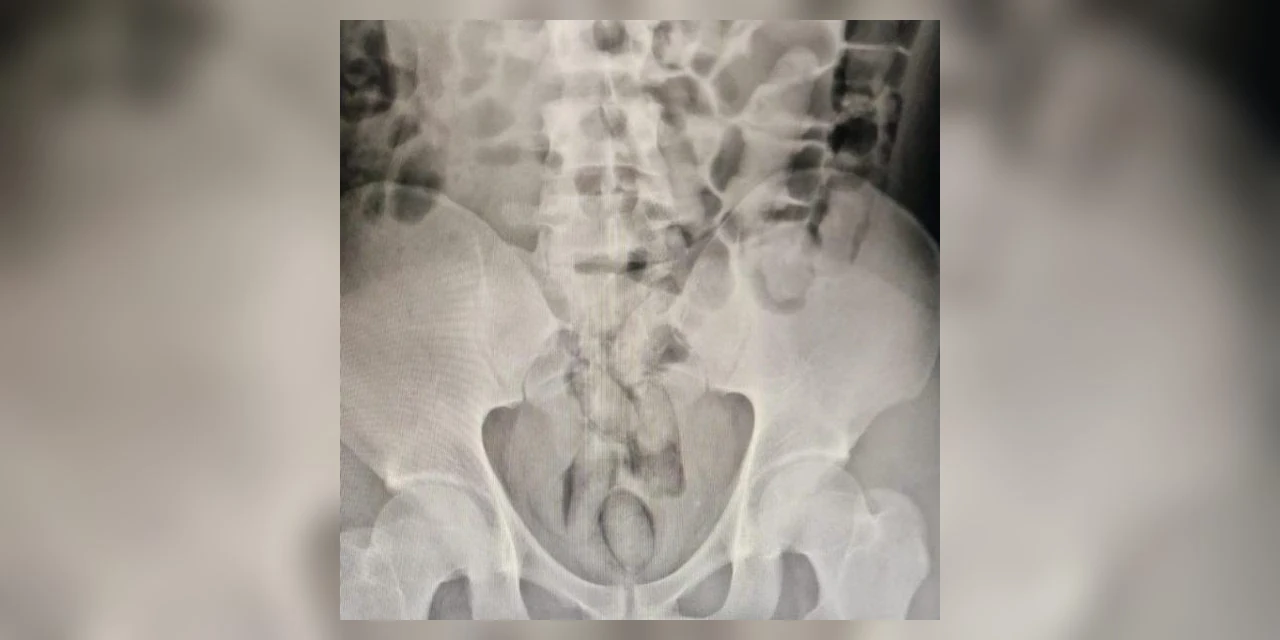

(Foto: Divulgação/Polícia Civil)

Um homem foi preso em flagrante neste domingo (18) após ser submetido a um raio-x e ser constatado que ele estava com 29 cápsulas de drogas em seu estômago. O caso ocorreu em São Lourenço do Oeste, Santa Catarina.

O suspeito passou por um raio-x que comprovou a existência de 29 cápsulas de cocaína dentro dele. Ele possuía antecedentes criminais e cumpria pena no Presídio de Chapecó, porem estava em saída temporária de 7 dias.